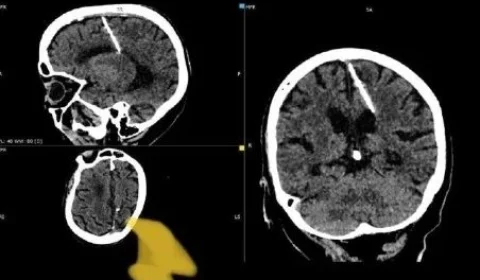

Idosa acha agulha de 3cm no cérebro após realizar exames na Rússia

Após 80 anos, idosa descobriu que tinha uma agulha de 3 centímetros cravada no cérebro desde a infância, vítima de uma tentativa de infanticídio.